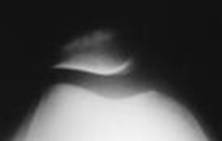

Radiografia rotulei - axial

Pacientul in DD; genunchiul flectat; planta pe masa; caseta tinuta cu o mana de pacient pe coapsa; membrul celalalt in extensie pe masa.

RC inclinata caudo-cranial; trece in intervalul cuprins intre condilii femurali si fata posterioara a rotulei. Film de 13x18 cm, in lung; marginea distala a casetei cu trei laturi de deget inaintea genunchiului; marginea mediala si cea laterala la egala distanta de partile moi.

Distanta F-F = 1m; fara Bk.

Rotula - axial